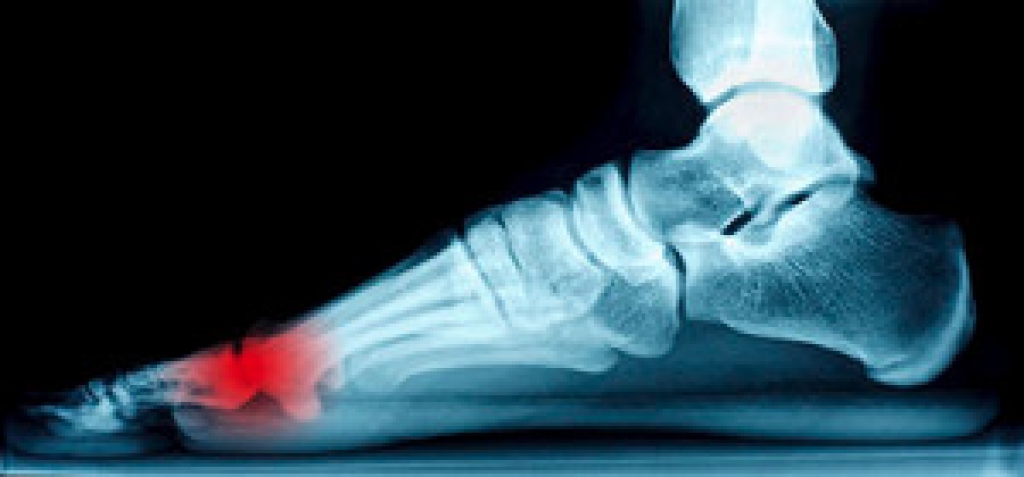

The sesamoid bones act like a pulley that enables the big toe to move normally. The sesamoids also absorb the weight placed on the ball of the foot. Turf toe occurs when the soft tissue surrounding the big toe is injured, which can cause sharp pain. Sesamoiditis is caused from pressure often resulting from inflammation of the sesamoid bones. This inflammation often occurs from overuse in athletic activities. People with high arches may be prone to developing sesamoiditis, as are frequent wearers of high heels. It is recommended to see a podiatrist for sesamoiditis, as they can properly diagnose and treat it.

Sesamoiditis is a condition of the foot that affects the ball of the foot. It is more common in younger people than it is in older people. It can also occur with people who have begun a new exercise program, since their bodies are adjusting to the new physical regimen. Pain may also be caused by the inflammation of tendons surrounding the bones. It is important to seek treatment in its early stages because if you ignore the pain, this condition can lead to more serious problems such as severe irritation and bone fractures.